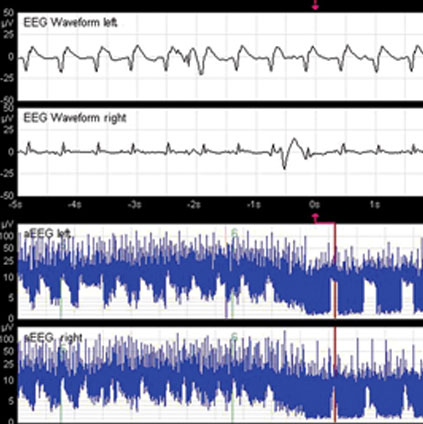

EEG brain wave patterns showing neonatal seizure activity for clinical diagnosis and monitoring

• EEG.

The management of neonatal seizures is challenging. They are difficult to diagnose and treat and are associated with adverse outcomes. The majority of neonatal seizures have no clinical correlates–they are electrographic only (subclinical) seizures. The gold standard investigation to diagnose seizures is continuous V-EEG preferably for about 24 hours, however, resource limitations are a hindrance to its universal applicability.